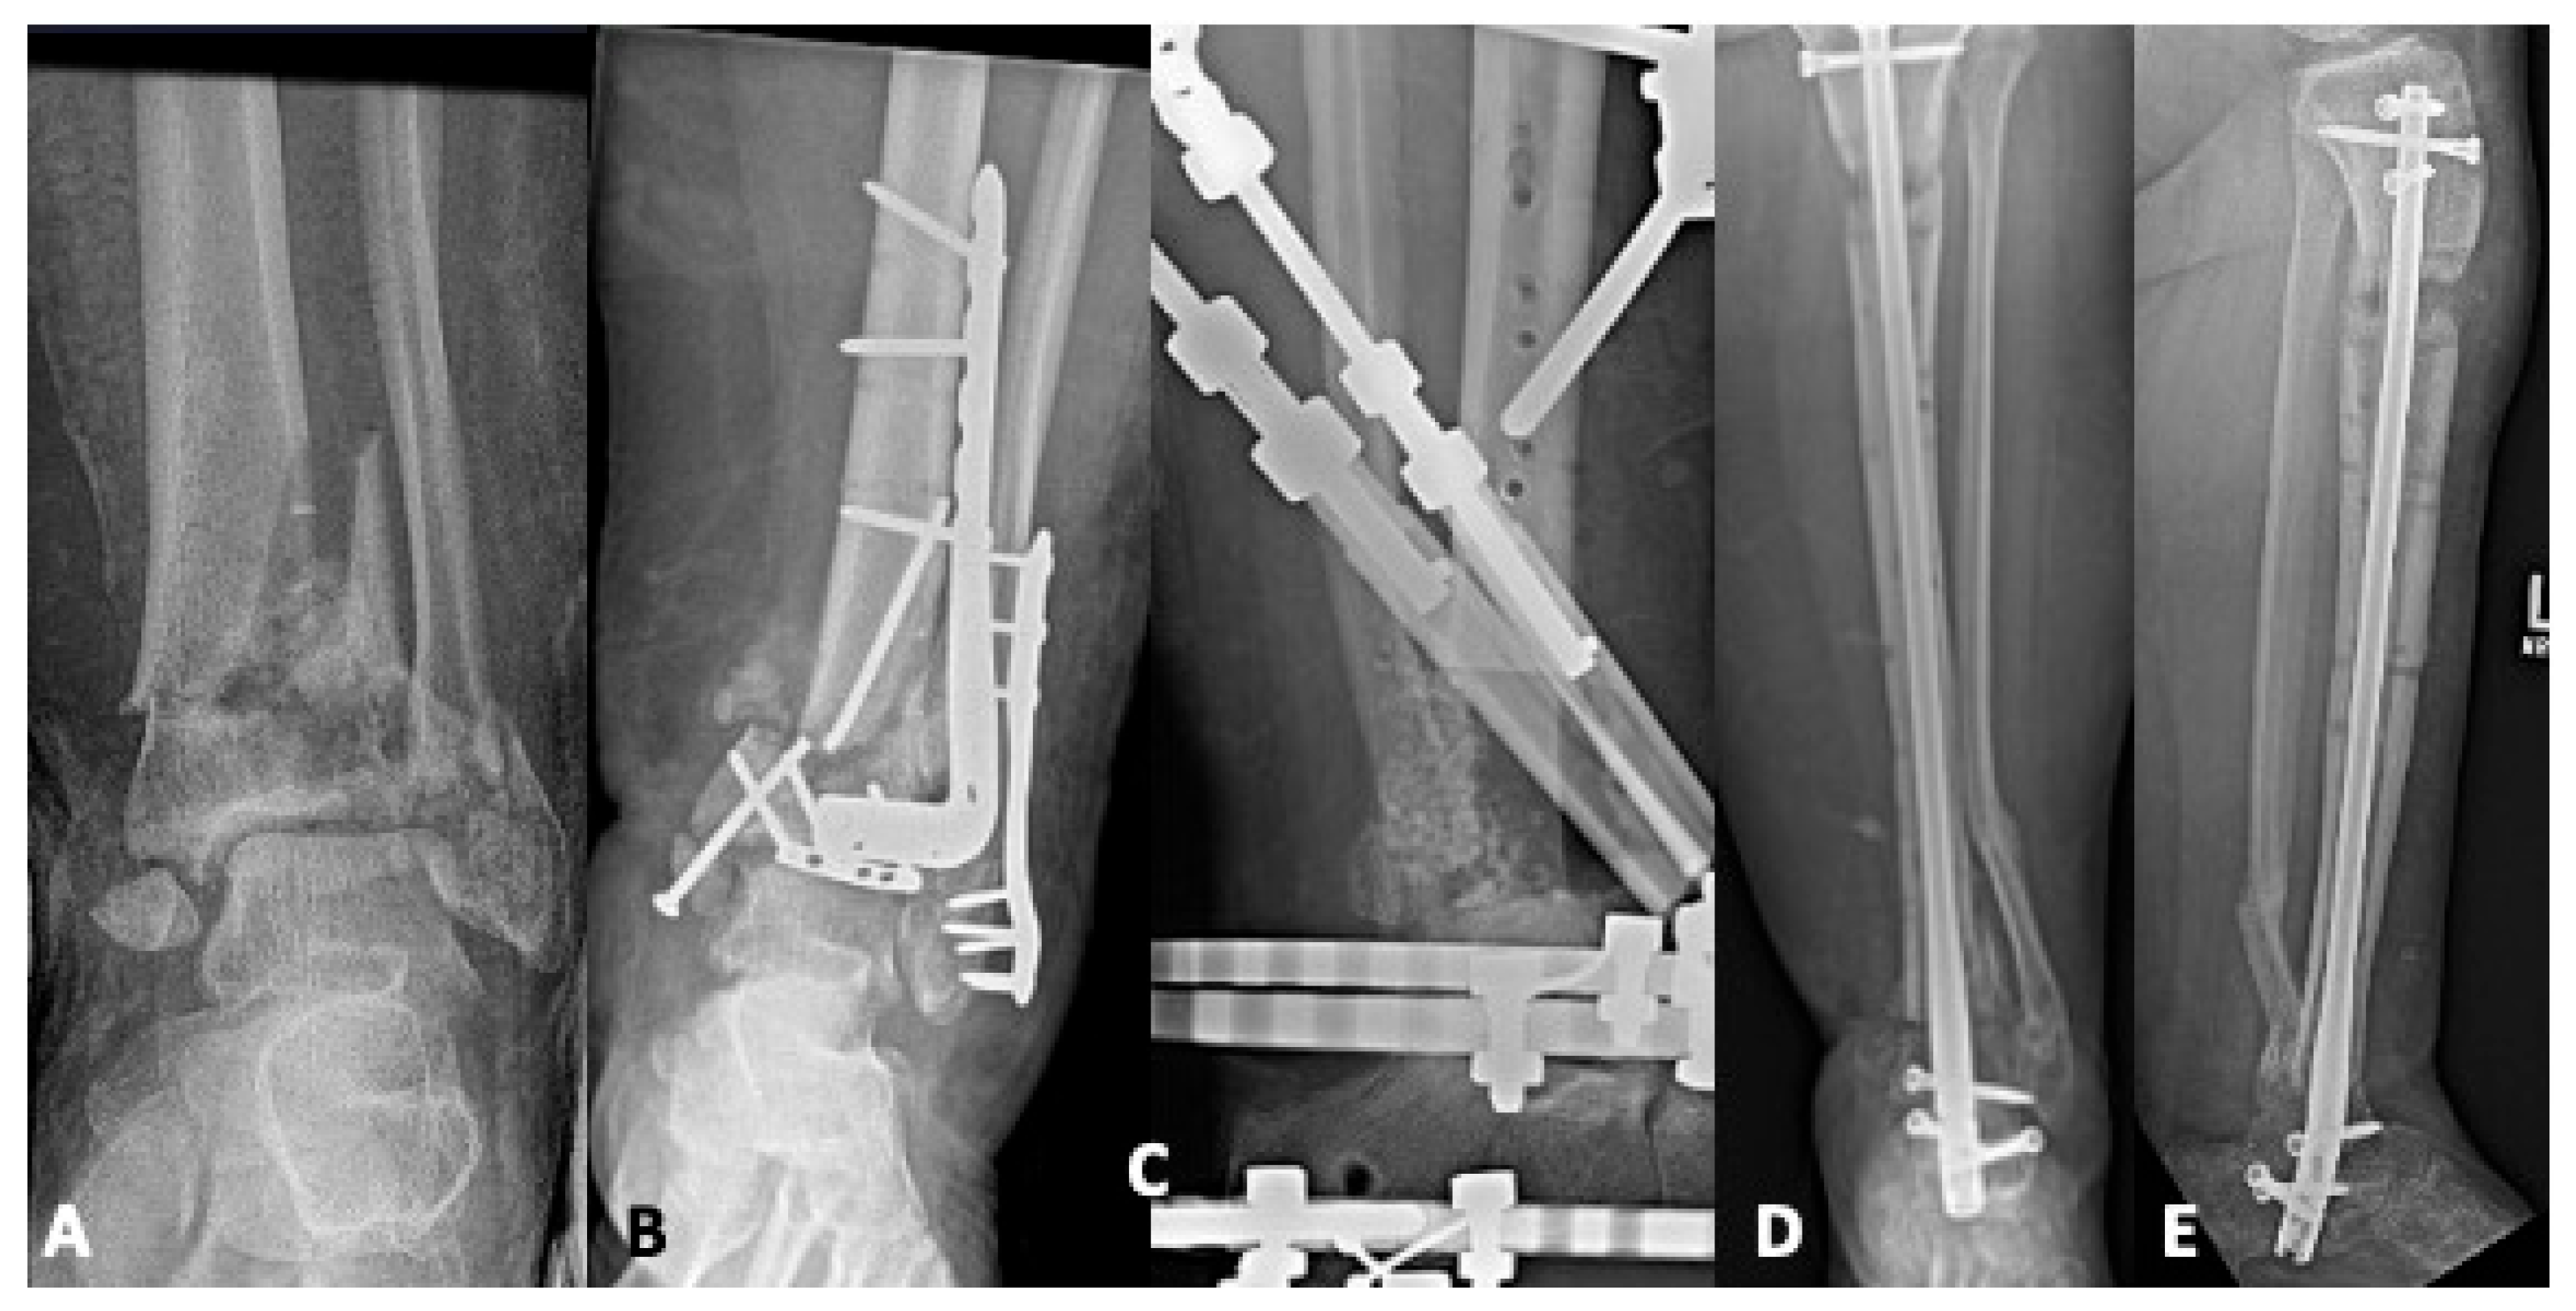

4.2. Bone Defects

5.1. Revision Operative Fixation